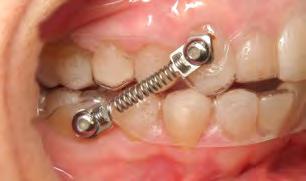

CORRECTOR DE CLASES II Y CLASES III

EFICIENCIA, FUERZAS CONSTANTES Y RESULTADOS PREDECIBLES.

La mejor alternativa a los elásticos sin colaboración del paciente.

GARANTIZA RESULTADOS CON TUS CASOS DE ORTODONCIA

CLASE II Y CLASE III CON ESTE REVOLUCIONARIO SISTEMA

Los resortes CS5® Niti son exclusivos de DynaFlex®, y utilizan una espiral patentada de fuerza instantánea (350 gr.), un muelle helicoidal cerrado y un extremo especialmente diseñado que se ajusta a nuestro pivote patentado tradicional y al nuevo pivote Twist-Lock™ o tradicional.

CS5® está hecho de un exclusivo material de níquel titanio con extremos de orificio especialmente construidos para mejorar la resistencia y durabilidad en un 40%. El nuevo resorte CS5® cargará fuerza al instante y se mantendrá extremadamente

constante durante todo el tratamiento con la confianza de un uso prolongado. El beneficio es una fuerza más suave y constante que se comporta mejor y dura más tiempo. El sistema CS5® es uno de los sistemas de clase II y clase III más exitosos que se utilizan en todo mundo debido a su simplicidad, efectividad y precio en comparación con otros sistemas disponibles en la actualidad. El CS5® es una mejora importante de un producto ya exitoso y ampliamente utilizado. Este es un sistema imprescindible para su inventario